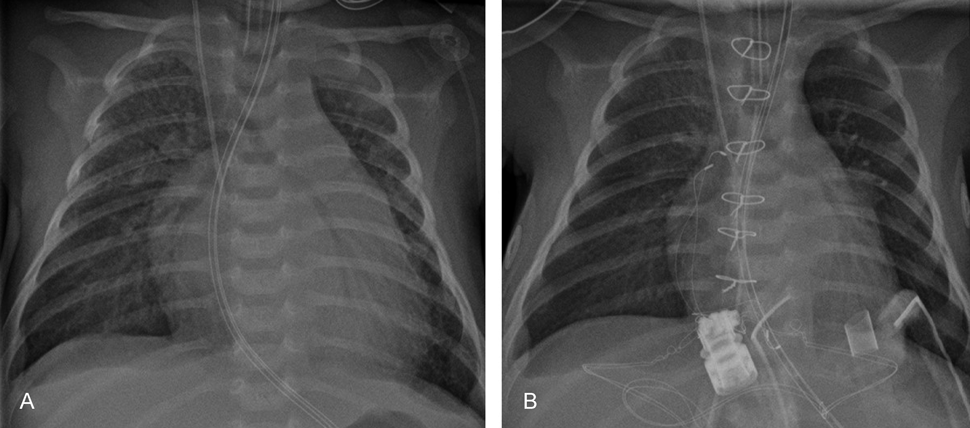

Fig. 2 X-ray in a child (1 month) with chronic lymphatic myocarditis with the phenotype of dilated cardiomyopathy and acute heart failure

A. X-ray with enlarged heart and with pulmonic congestion prior (acute heart failure) and B. post implantation of a left ventricular assist device (LVAD, Berlin Heart EXCOR® 10cc) with reduced heart size and congestion. The endomyocardial biopsy revealed a virus negative chronic lymphocytic myocarditis. This is showing the acute therapeutic effect of VAD therapy in order to complete diagnostic workup.